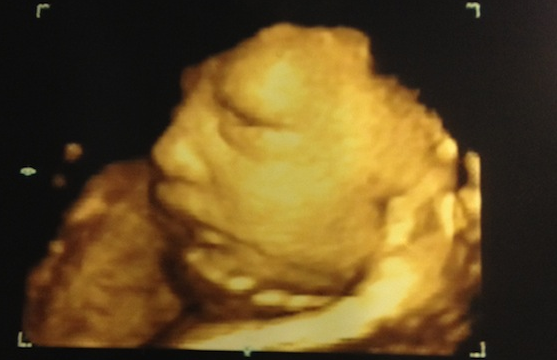

Jenni is expecting her first child with her fiancé Rodger Mathews.

But despite all the pain, Jenni can't wait for her little one's arrival next month.

“But she’s perfect and because of that I’ll take all the back pain in the world! I can’t wait to meet her in a few weeks!!!!”